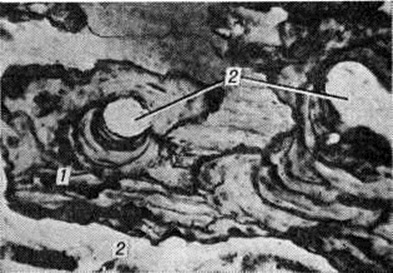

При микроскопическом исследовании в поражённых костях различают предсуществующую и новообразованную костную ткань. Предсуществующая ткань сохраняет функциональный характер архитектоники костных структур, в ней определяют специфичную для Педжета болезнь резкую мозаичность, хаотичность рисунка костных пластин, неравномерность окраски, явления аутолитического рассасывания костного вещества, наиболее выраженного по ходу сосудистых каналов (рисунок 7). В предсуществующем костном веществе нередки микропереломы. Возникновение этих изменений отражает характер перераспределения силовых нагрузок, интенсивность патологический перестройки в деформированном костном органе.